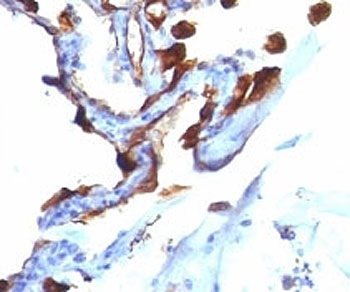

IHC analysis of formalin-fixed, paraffin-embedded human lung carcinoma stained with Cytokeratin 8/18 antibody (clone C-51).